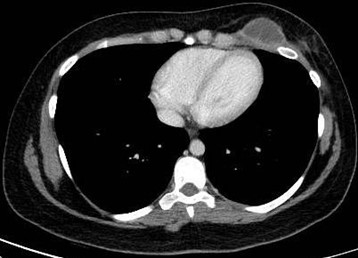

Paciente femenina de 26 años de edad, sin antecedentes patológicos de relevancia, sin dosis de vacuna BCG. Cursa con cuadro clínico de ocho meses de evolución, caracterizado por dolor en región pectoral izquierda intermitente, que se exacerba a la inspiración profunda. En el último mes se palpa masa indurada dolorosa a la palpación a nivel del cuadrante inferior interno de mama izquierda, motivo por el cual se realiza ecografía de partes blandas, donde se observa a nivel retropectoral en íntimo contacto con la parrilla costal imagen hipoecogénica de bordes delimitados, avascular al Doppler color por lo cual se solicita TC de tórax con EV. En ella se observa en topografía del cuarto espacio intercostal, imagen hipodensa con realce periférico tras la administración del contraste que desplaza por efecto de masa el parénquima pulmonar adyacente y se proyecta a la pared torácica anterolateral izquierda; mide 40 mm x 55 mm. Además, se visualiza otra imagen de similares características de base pleural en contacto con el octavo arco costal posterior izquierdo que mide 6 mm x 11 mm.

Cuatro meses posteriores a la PAAF la paciente refiere persistencia de dolor y aumento de tamaño de la masa asociado a eritema en región mamaria, por lo cual se realiza TC de tórax con contraste EV donde se observa imagen hipodensa ya conocida, con realce periférico tras la administración de contraste, con aumento de tamaño y bordes lobulados.